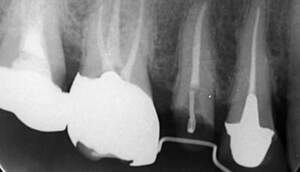

| 根の中の薬が十分に充填されておらず、根の先が周りと比べて黒くなっており、炎症があると判断できます。 | 根の中にしっかりとお薬を緊密に充填しましたが、まだ根の先に黒くなっている部分があります。 |

左は歯を挺出するために装置をつけた直後です。

右は挺出が終わり、コアをセットしたところです。

歯根の位置が歯冠側によっているのがわかります。